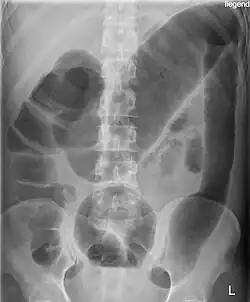

Massively dilated colon with air-fluid level can be seen on abdominal radiograph or CT scan.[7][8]

To diagnose toxic megacolon (TM), the criteria include: (a) radiographic evidence of the colon being dilated to over 6 cm, especially in the transverse colon; (b) at least three of the following symptoms: fever (over 38.6°C), rapid heartbeat (over 120 beats per minute), high white blood cell count (over 10.5 × 10³/μL), or anemia; and (c) signs of severe illness like low blood pressure, dehydration, confusion, or electrolyte imbalances.[9]

Imaging, particularly CT scans, is crucial for diagnosis and to check for complications that may need immediate surgery. X-rays are used to track the size of the colon. Common imaging findings include dilation of the transverse or right colon, mucosal ulcers, thinning of the colon wall, air-fluid levels, and pseudopolyps. Blood tests typically show high white blood cells, anemia from blood loss, metabolic alkalosis, low potassium, low albumin, and elevated markers of inflammation.[9]